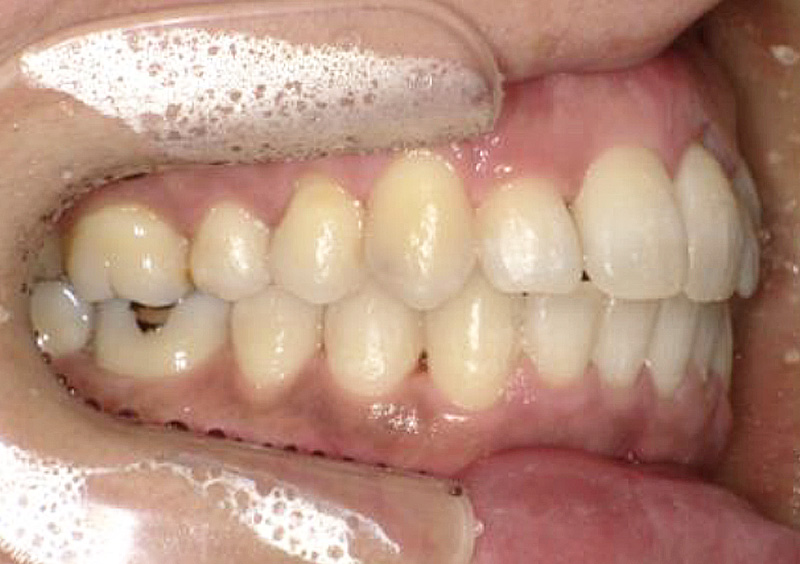

大人の矯正治療 歯ががたついている(叢生) 2025.10.22 【マルチブラケット矯正】前歯のがたつきが気になる 治療前 治療後 担当医 一瀬 悠依華 先生 主訴 前歯のがたつきが気になる 期間 1年 費用 39万円 治療内容 マルチブラケット装置(上下前歯部分矯正) 治療に伴うリスク 歯根吸収、歯肉退縮 関連症例